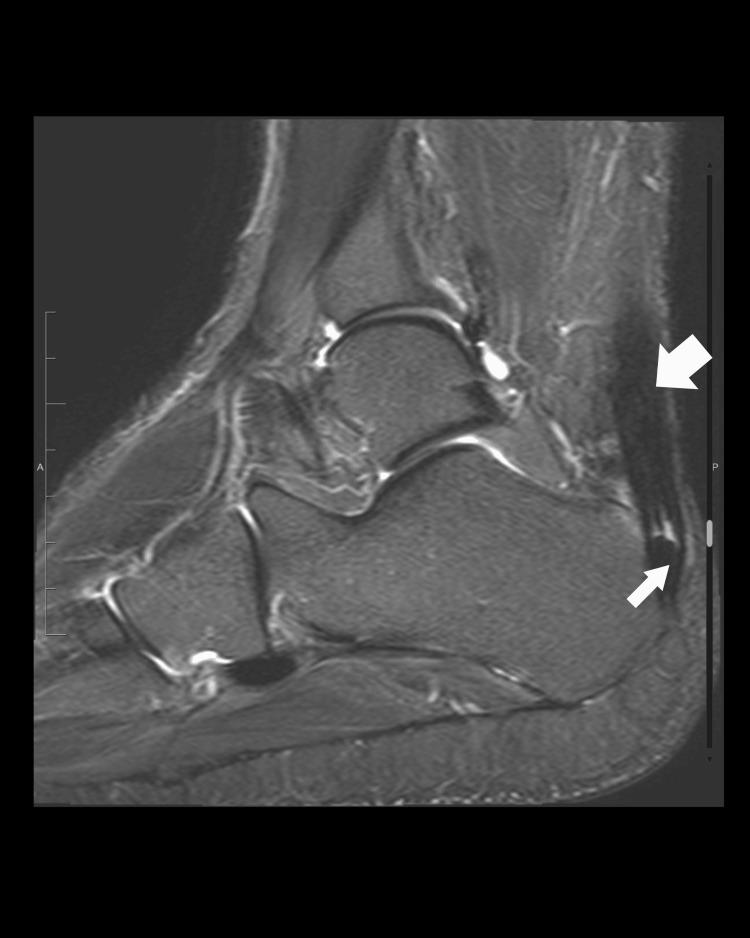

Alkaptonuria (AKU) is a rare metabolic condition caused by mutations within a gene coding for homogentisate 1,2 dioxygenase enzyme involved in the tyrosine catabolism pathway. This mutation will result in the accumulation of homogentisic acid (HGA) in the body. AKU is a multi-systemic slowly progressing disease. The onset of its clinical presentation may vary based on the extensive disposition of the HGA. Initially, it might be asymptomatic, and symptoms usually appear in the second or third decades due to the formation of HGA, melanin compounds that accumulate in the cartilage leading to ochronosis. Furthermore, by the fourth or fifth decade, ochronotic arthropathy occurs, along with other extra-articular complications such as cardiovascular manifestations (e.g., valvular heart disease), renal and prostatic stones, and hypothyroidism. Management of this condition is mainly symptomatic, focusing on the treatment of its complications. Recently, the use of nitisinone (NTBC) has shown stabilization of disease manifestations. In this report, we present in detail the first AKU-diagnosed patient, including the clinical presentations, radiological findings, genetic results, and clinical outcomes, from the main tertiary hospital in Bahrain. Moreover, we conducted a thorough literature review on this rare condition.

黑尿症(AKU)是一种罕见的代谢性疾病,由参与酪氨酸分解代谢途径的尿黑酸1,2双加氧酶基因发生突变引起。这种突变会导致尿黑酸(HGA)在体内蓄积。AKU是一种多系统缓慢进展的疾病。其临床表现的发作可能因HGA的广泛分布而有所不同。最初,它可能无症状,症状通常在第二或第三个十年出现,这是由于HGA形成了黑色素化合物,这些化合物在软骨中蓄积导致褐黄病。此外,到第四或第五个十年,会出现褐黄病性关节病,以及其他关节外并发症,如心血管表现(如瓣膜性心脏病)、肾和前列腺结石以及甲状腺功能减退。这种疾病的治疗主要是对症治疗,重点是治疗其并发症。最近,使用尼替西农(NTBC)已显示出疾病表现得到稳定。在本报告中,我们详细介绍了巴林主要三级医院诊断出的首例AKU患者,包括临床表现、影像学检查结果、基因检测结果和临床结局。此外,我们对这种罕见疾病进行了全面的文献综述。